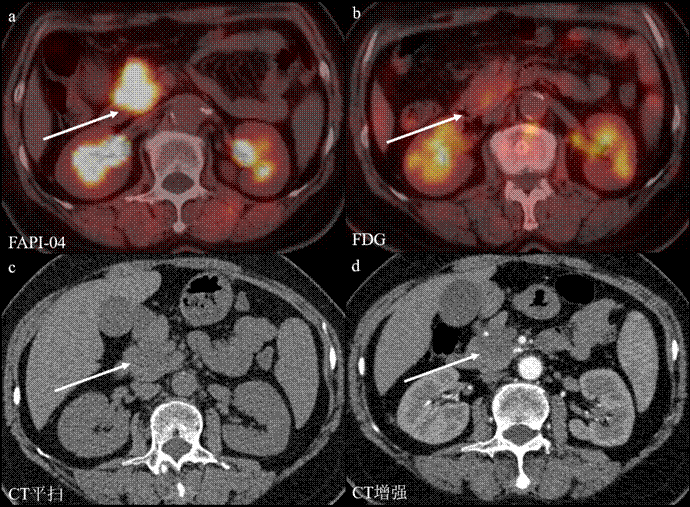

图1:不同检查方法显示胰腺癌。a. FAPIPET/CT显像:病灶呈高摄取,显示清楚;b. FDG PET/CT显像:病灶局部轻度摄取,显示尚可;c. CT平扫:病灶呈等及稍低密度影,显示不清;d. CT增强:病灶表现为乏血供结节,显示尚可。